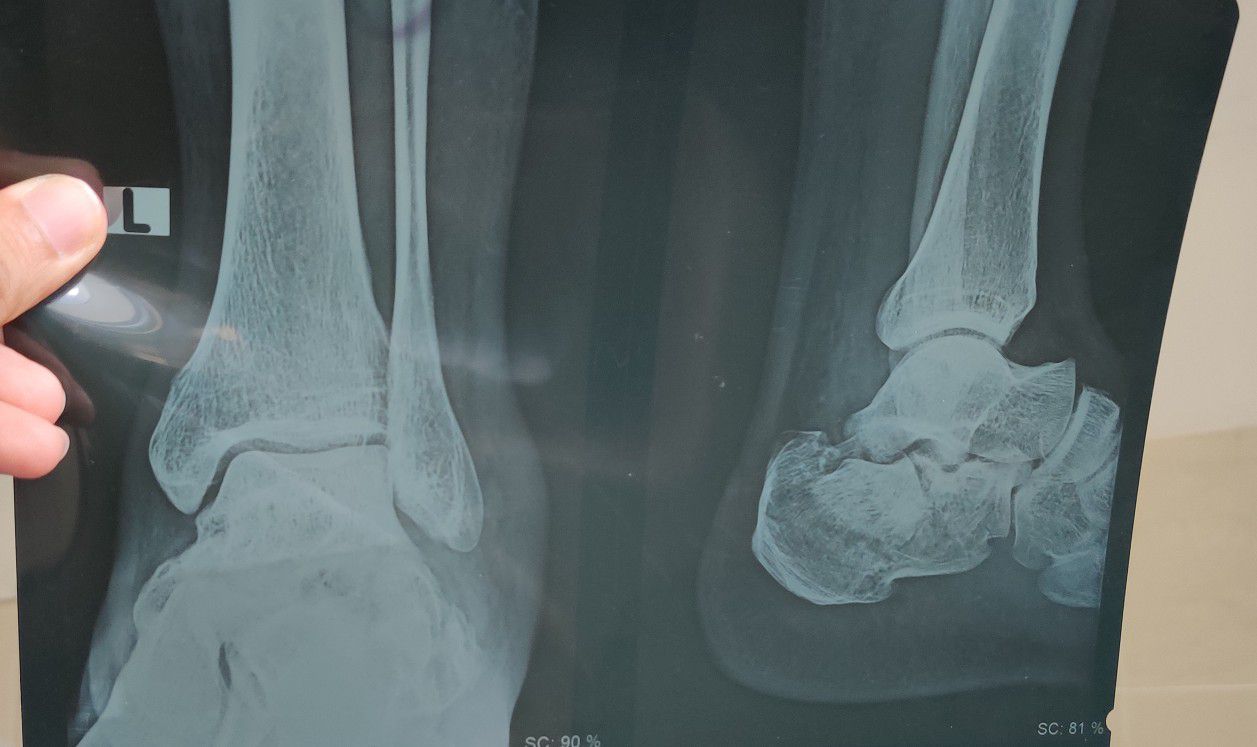

Calcaneum Fracture

Fracture

Foot

Calcaneus